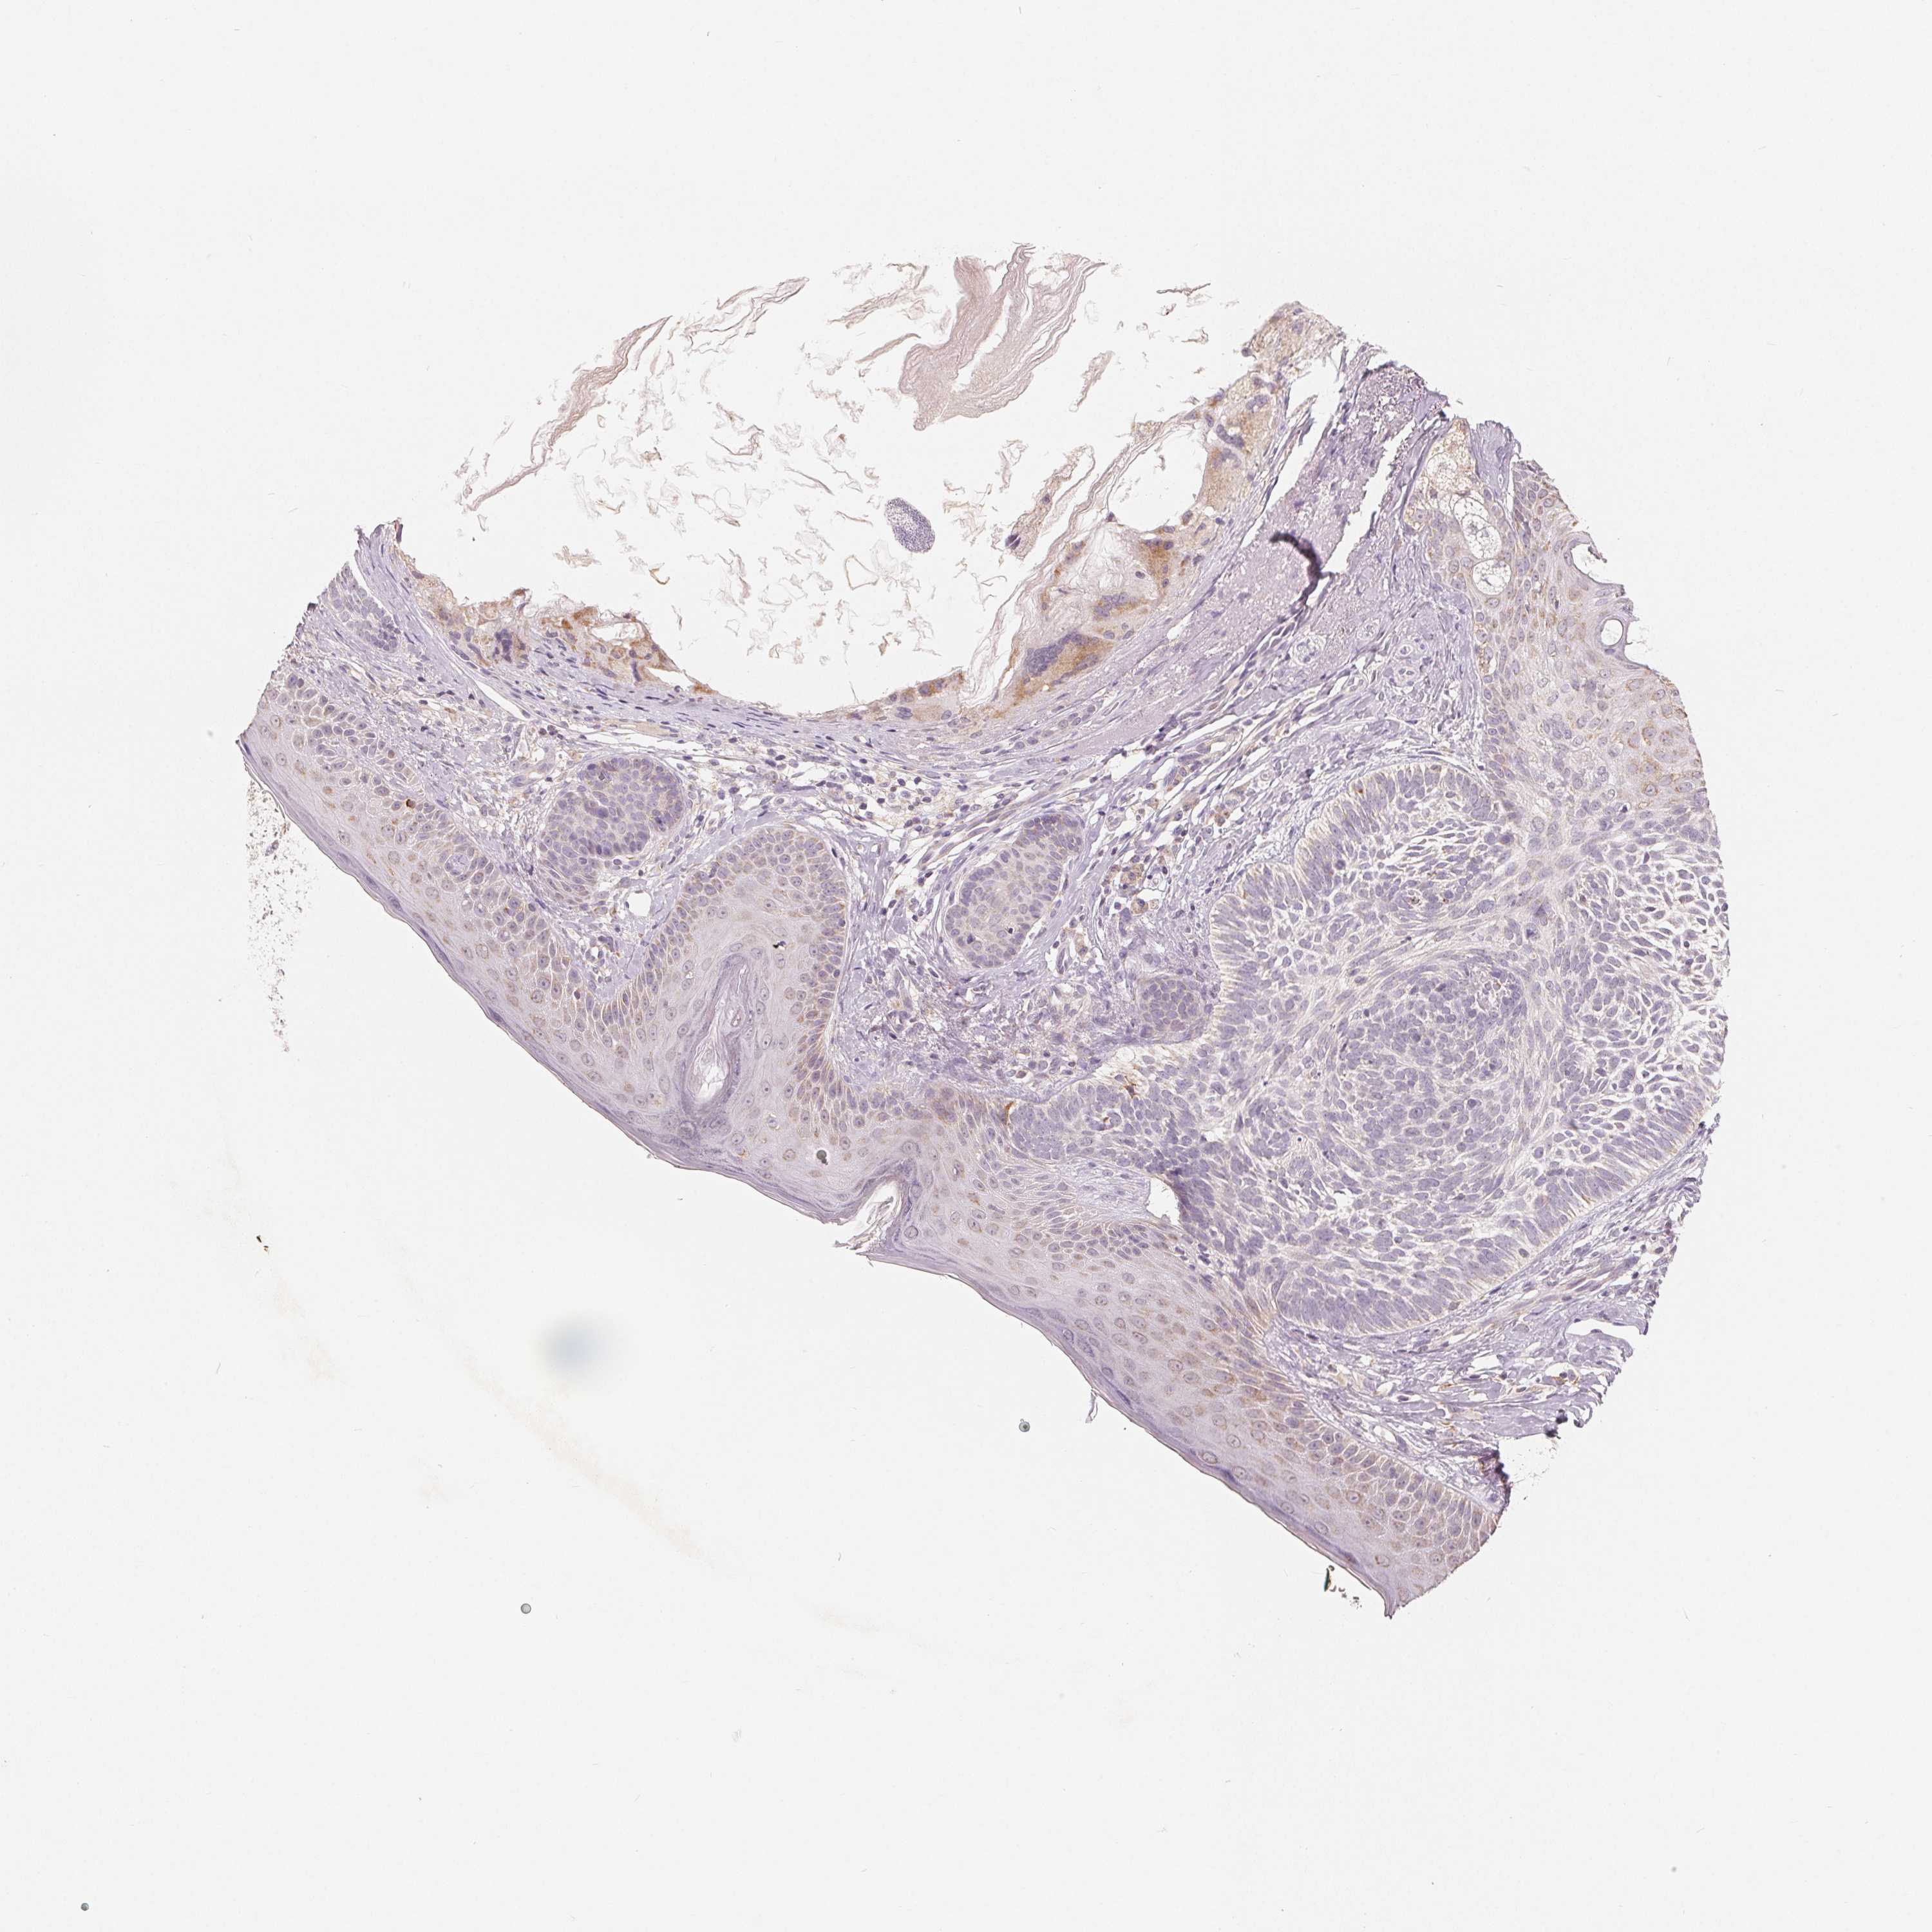

SKIN CANCER - Protein expressioni

A mouse-over function shows sample information and annotation data. Click on an image to view it in a full screen mode. Samples can be filtered based on level of antibody staining by selecting one or several of the following categories: high, medium, low and not detected. The assay and annotation is described here.

Antibody stainingi

Antibody staining in the annotated cell types in the current human tissue is reported as not detected, low, medium, or high, based on conventional immunohistochemistry profiling in selected tissues. This score is based on the combination of the staining intensity and fraction of stained cells.

Each image is clickable and will lead to virtual microscopy that enables deeper exploration of all samples and also displays staining intensity scores, fraction scores and subcellular localization as well as patient and tissue information for each sample.

Antibody HPA016464

Basal cell carcinoma

Squamous cell carcinoma, NOS

Squamous cell carcinoma, metastatic, NOS

BCC, high aggressive